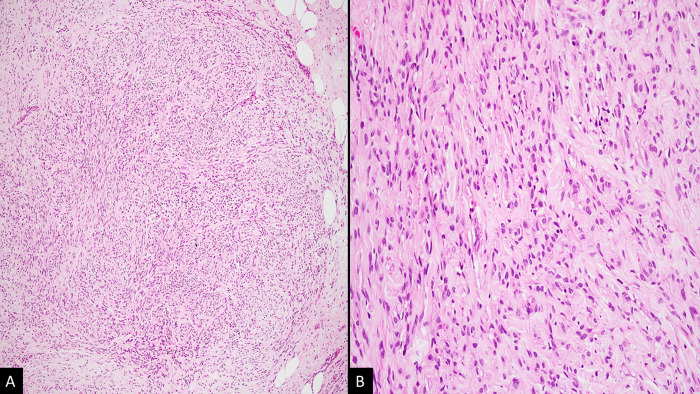

Mammary myofibroblastoma (MM) is an uncommon, benign mesenchymal neoplasm with a favourable prognosis. Its resemblance to various other benign and malignant lesions of the breast makes precise diagnosis challenging when examining biopsy samples. The rarity of mammary myofibroblastoma in India and worldwide underscores the importance of our case report, as we aim to contribute to the existing literature and expand the knowledge base of this neoplasm. Furthermore, we have delved into the diagnostic complexities associated with this lesion and highlighted the ancillary techniques employed to achieve an accurate and reliable diagnosis.